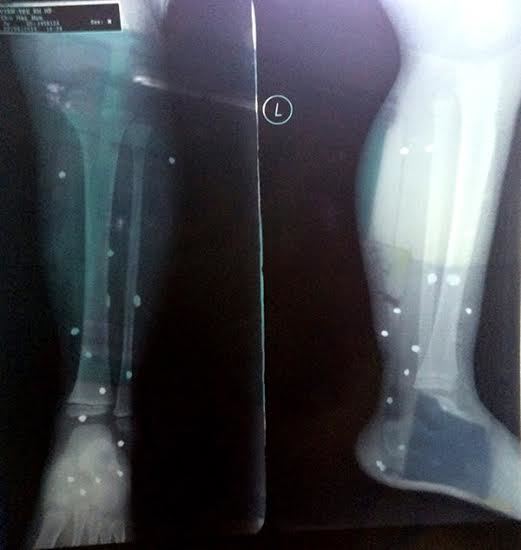

| Thương tích của cháu Nam |

Con trai anh Tấn là cháu Chu Hải Nam (SN 2009) đang đứng ở cửa dính đạn bị thương tích ở cẳng chân trái.

Cháu Nam sau khi đưa đi cấp cứu ở bệnh viện địa phương đã phải chuyển lên bệnh viện Trung ương để tiến hành phẫu thuật gặp bỏ đạn chì trong cơ thể.

Sơ bộ xác định thương tích ở vùng cẳng chân và bàn chân trái của cháu Nam có 16 dị vật.